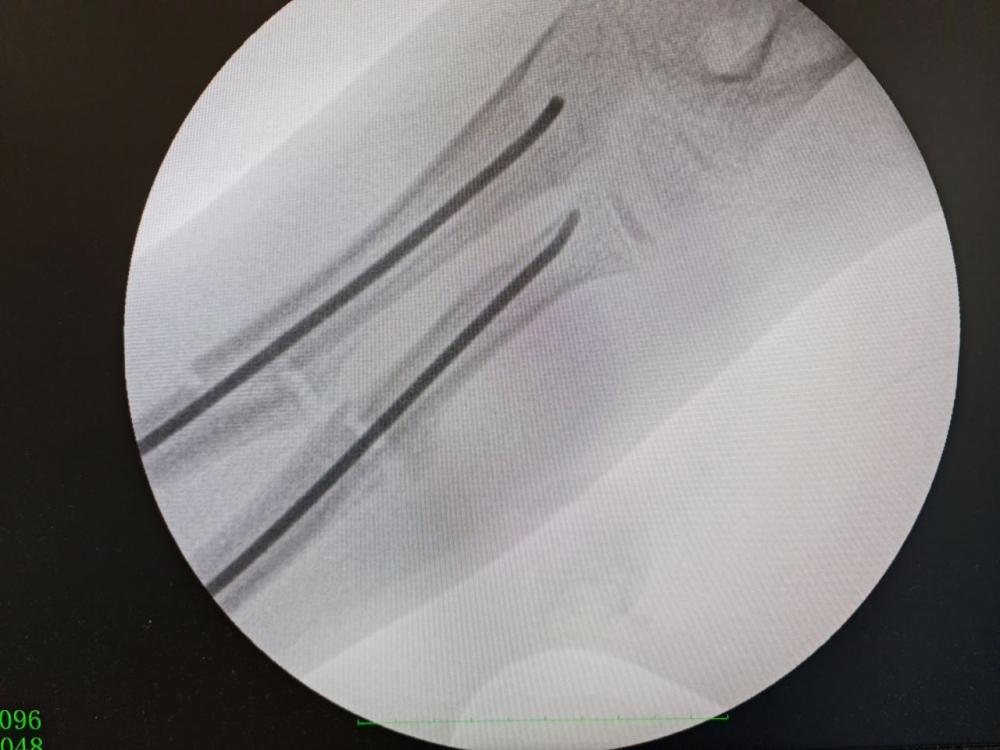

Саме тому і вирішили провести дитині так звану «остеоклазію кісток передпліччя із внутрішньою фіксацією титановими еластичними стрижнями».

«Остеоклазія- це операція штучного перелому в місці зрощення під рентген-контролем з метою співставити уламки кісток та зафіксувати їх за допомогою титанових еластичних стрижнів", - розповідають медики.